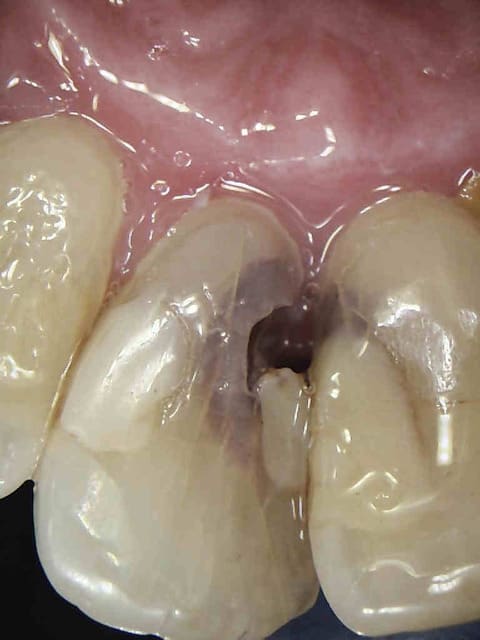

> tailles sous gingivales sur dents vivantes : est-ce justifié sur une molaire ?

Ca dépend du volume d'ancien matériau que t'as dégagé, des infiltrations sous ces dites obturations, etc...C'est pas un dogme, mais en reconstituant on se donne souvent bonne conscience grace à la hauteur du moigon. Sur DV tu peux pas tricher.

Endos sans digue, avec de la carie résiduelle, la gutta/ciment ne remplit pas toute la lumière du canal, pas de respect de l'espace biologique, effet férule minimaliste.....

Vu les autres dents le patient ne mérite peut être pas mieux et l'indication est là mieux posée, mais tu te positionnes comme un pro de l'endo puisque tu en ferais souvent et là, c'est pas flagrant...